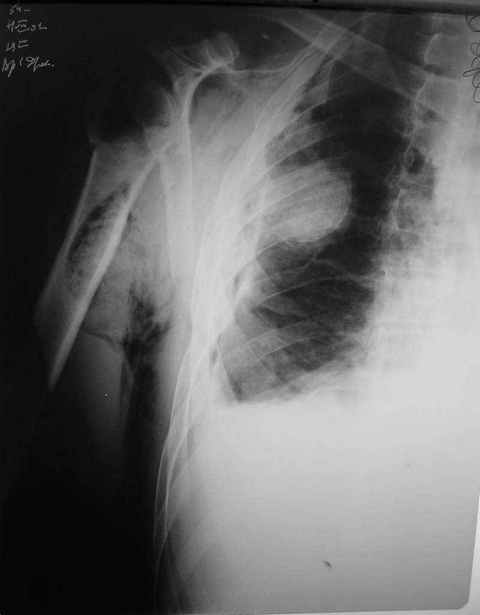

Правый плечевой сустав умеренно деформирован. По внутренней поверхности плеча имеется кровоподтек. При пальпации плечевого сустава имеется умеренная болезненность. Активные и пассивные движения болезненные. Снижена чувствительность по тыльной поверхности пальцев кисти и отсутствует активное разгибание кисти и пальцев. Имеется подкожная эмфизема шеи, верхней половины грудной клетки (рис 1, 2). На рентгенограмме: оскольчатый перелом головки плечевой кости со значительным смещением, перелом 2-3 ребер справа, тканевая эмфизема (рис 3). КТ при поступлении: перелом головки плечевой кости в области анатомической шейки со смещением отломка головки в грудную полость, правосторонний гидроторакс, перелом 2-3-4 ребер справа. (рис 4). Через двое суток после поступления выполнена операция: атипичная торакотомия, эвакуация свернувшегося гемоторакса, удаление инородного тела (головки плечевой кости) из плевральной полости (при этом выявлено имеющееся повреждение париетального и висцерального листков плевры) (рис. 5), дренирование плевральной полости, замещение проксимального конца плечевой кости спейсером из костного цемента с антибиотиком (рис. 6). Послеоперационный период протекал гладко. При контрольной рентгенографии положение спейсера удовлетворительное (рис. 7, 8). Дренаж из плевральной полости удален через 3 суток после вмешательства. Послеоперационная рана зажила первичным натяжением. Через 12 дней после операции больной выписан на амбулаторное лечение.